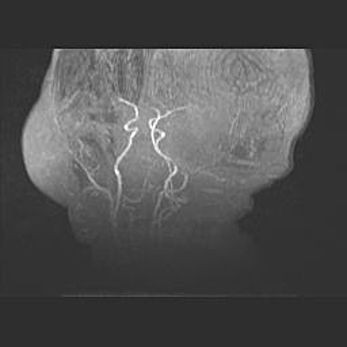

Подострая гематома правой гемисферы мозжечка.

Наружная гидроцефалия.

Возраст: 15 дней

Вес: 3100 г

Пол: женский

Окружность головы: 37 см

Срок гестации: 35-36 недель

При открытой наружной форме гидроцефалии у новорожденных расширяются и переполняются субарахноидные пространства.

Кровоизлияния в мозжечок имеют две клинико-анатомические формы: полушарные гематомы и кровоизлияния в червь.

К появлению этой патологии может привести: повреждения головного мозга, возникающие в результате асфиксии и гипоксии плода при беременности, или травмы во время родов. Редко гематома мозжечка может быть результатом первичной коагулопатии и сосудистой мальформации, диссеминированном внутрисосудистом свертывании, изоиммунной тромбоцитопении.